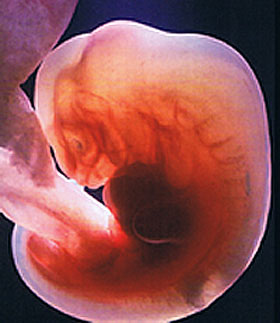

S'il y a une 4ème semaine d'obstétrique, alors il est trop tôt pour parler du fœtus. Le zygote passe progressivement au stade de l'embryon. L'enfant à naître est maintenant un bloc de cellules presque invisible, que les scientifiques appellent morula. Au microscope, il ressemblera à une baie recouverte de «boutons». Si la consolidation de la morula dans la cavité utérine ne s'est pas encore produite, elle aura certainement lieu. Et puis la vraie magie cellulaire commence.

La taille du futur fœtus au cours de la 4e semaine d'obstétrique est comparable à la «graine de pavot». Son poids est d'environ 0,5 g et sa hauteur de 0,36 à 1 mm. Cependant, ce sont des données littéralement momentanées. L'embryon augmente rapidement en raison d'une division cellulaire constante.

La structure de l'embryon

Les médecins utilisent souvent le concept du disque germinal, qui forme la feuille germinale. Ce sont des couches spéciales de cellules:

- la couche interne (endoderme) donnera naissance au tube digestif, au foie et aux poumons, ainsi qu'au pancréas;

- la couche intermédiaire (mésoderme) est constituée des futurs reins, muscles, cœur et vaisseaux sanguins, ainsi que du squelette du bébé;

- la couche externe (ectoderme) est responsable de la formation du système nerveux, de la tête (y compris les yeux, les dents et les cheveux), ainsi que de la peau.

Organes germinatifs supplémentaires

Le miracle de la nature réside également dans le fait qu'une seule cellule fécondée, lorsqu'elle est divisée, fournit au bébé tout ce dont il a besoin. Y compris les repas complets. Cela se fait par les soi-disant organes extra-germes. Il y en a trois:

- chorion: une sorte de sac poilu qui devient plus tard un placenta;

- amnion est la future vessie fœtale, le «conditionnement» solide du fœtus;

- sac vitellin - approvisionnement alimentaire pour l'embryon.

Le dernier organe extra-germinal est particulièrement important. C'est son dysfonctionnement ou sa pathologie qui peut conduire à une fausse couche. Selon l'état du sac vitellin, un spécialiste en échographie recevra des données importantes sur la grossesse et l'embryon.